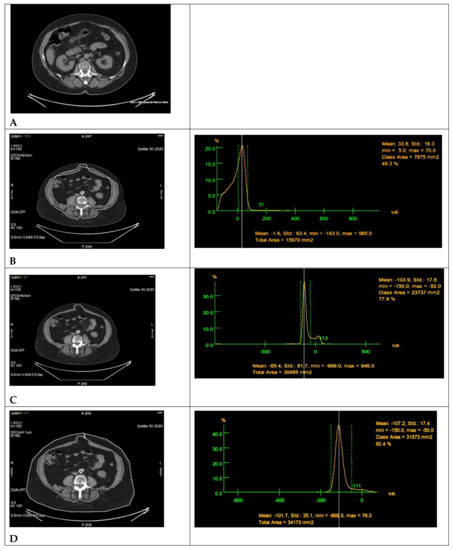

2.2. Radiomics Parameters